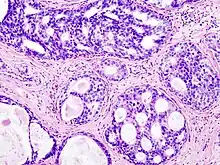

Ductal carcinoma in situ (DCIS) in breast tissue, cell nuclei (blue-purple), extracellular material (pink).

H&E is the combination of two histological stains: hematoxylin and eosin. The hematoxylin stains cell nuclei a purplish blue, and eosin stains the extracellular matrix and cytoplasm pink, with other structures taking on different shades, hues, and combinations of these colors.[5][6] Hence a pathologist can easily differentiate between the nuclear and cytoplasmic parts of a cell, and additionally, the overall patterns of coloration from the stain show the general layout and distribution of cells and provides a general overview of a tissue sample's structure.[7] Thus, pattern recognition, both by expert humans themselves and by software that aids those experts (in digital pathology), provides histologic information.

Hematoxylin principally colors the nuclei of cells blue or dark-purple,[6][15][14] along with a few other tissues, such as keratohyalin granules and calcified material. Eosin stains the cytoplasm and some other structures including extracellular matrix such as collagen[5][7][14] in up to five shades of pink.[8] The eosinophilic (substances that are stained by eosin)[5] structures are generally composed of intracellular or extracellular proteins. The Lewy bodies and Mallory bodies are examples of eosinophilic structures. Most of the cytoplasm is eosinophilic and is rendered pink.[10][15] Red blood cells are stained intensely red.